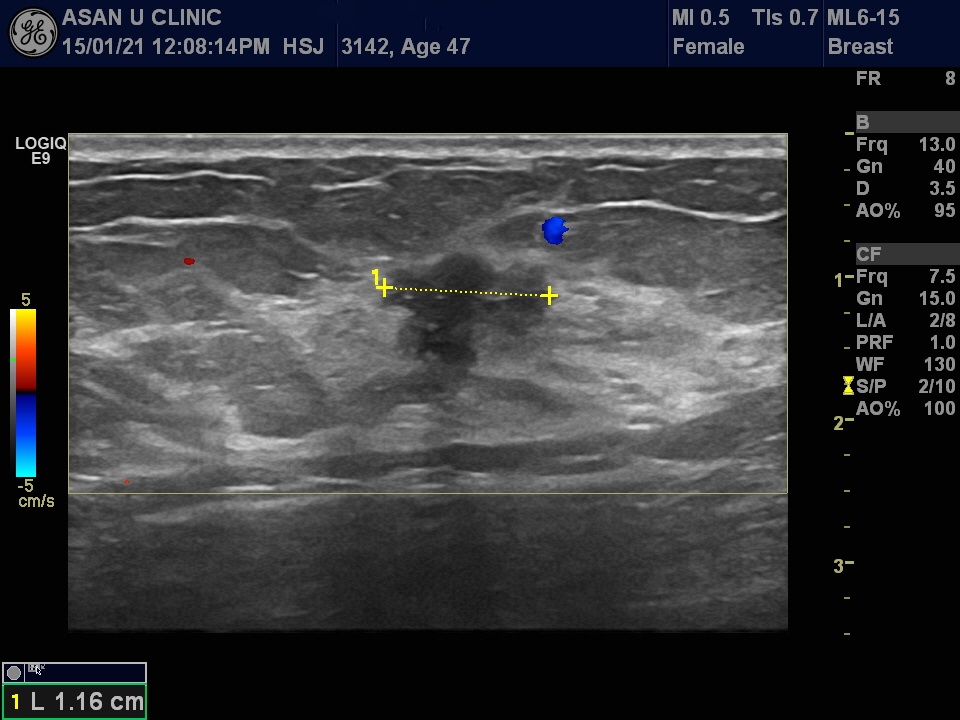

건강검진상 이상소견으로 내원한 만 47세의 여성분입니다.

유방촬영상 오른쪽 유방의 상내측과 겨드랑이에 음영이 보였고

초음파 유도하에 조직검사를 시행하여

우측 유방의 침윤성 유관암과 겨드랑이 림프절 전이로

진단되었습니다.

초음파 영상처럼 유방의 혹이 2cm도 안되는 작은 크기임에도 불구하고

겨드랑이에 림프절까지 진행이 되어있어 안타까움을 느낍니다.